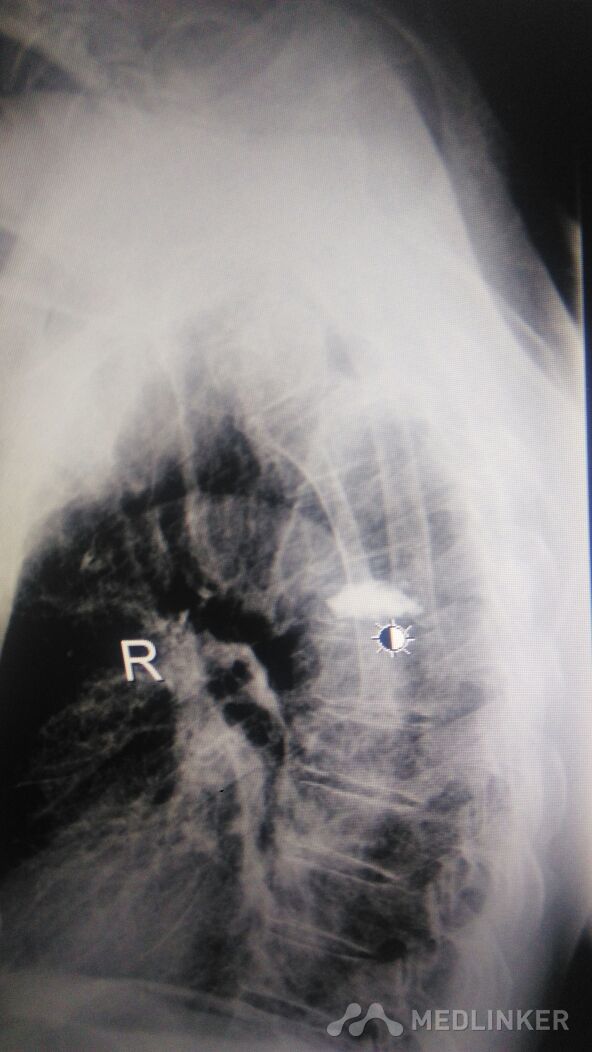

外科活动+胸椎体成形术。术后到术前很成形功。